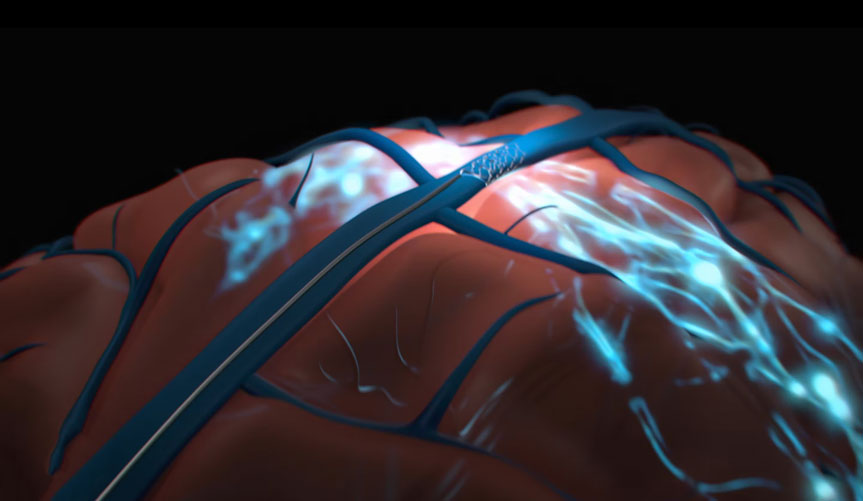

Medical Animation

Neurology